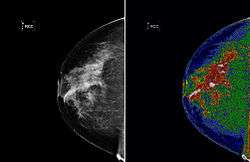

A region of interest (often abbreviated ROI), is a selected subset of samples within a dataset identified for a particular purpose.[1] The concept of a ROI is commonly used in many application areas. For example, in medical imaging, the boundaries of a tumor may be defined on an image or in a volume, for the purpose of measuring its size. The endocardial border may be defined on an image, perhaps during different phases of the cardiac cycle, for example end-systole and end-diastole, for the purpose of assessing cardiac function. In geographical information systems (GIS), a ROI can be taken literally as a polygonal selection from a 2D map. In computer vision and optical character recognition, the ROI defines the borders of an object under consideration. In many applications, symbolic (textual) labels are added to a ROI, to describe its content in a compact manner. Within a ROI may lie individual points of interest (POIs).

Medical imaging

Medical imaging standards such as DICOM provide general and application-specific mechanisms to support various use-cases.